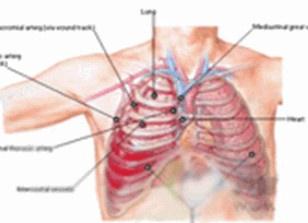

• 胸部創(chuàng)傷

發(fā)生于胸部的創(chuàng)傷,在平時(shí)或戰(zhàn)時(shí)都較常見,據(jù)估計(jì)約占全身創(chuàng)傷的1/4,在創(chuàng)傷死亡者中,約20%主要因胸部創(chuàng)傷所致。但胸部創(chuàng)傷在醫(yī)院內(nèi)死亡的百分比卻不高,原因是嚴(yán)重的胸部...